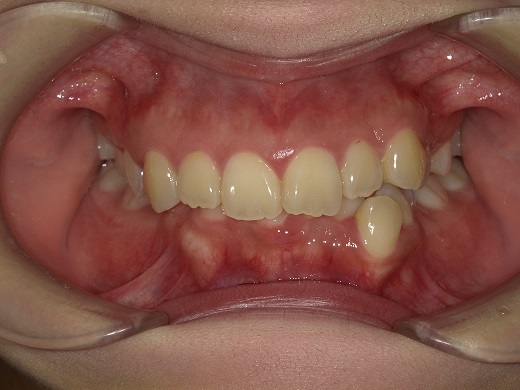

治療前正面